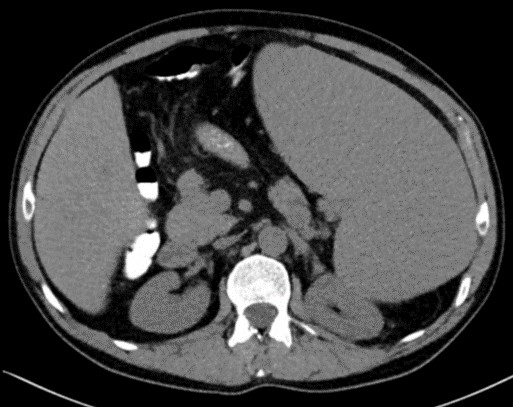

Los estudios complementarios que incluyeron biopsia de médula ósea, mielograma en sangre periférica, ecografía abdominal y TAC toraco-abdominal únicamente demostraron marcada esplenomegalia y dilatación del eje esplenoportal sin otros hallazgos patológicos, ni tan siquiera en el estudio histológico de la médula ósea (ver imagen 1).

Imagen 1: TAC abdomino-pélvico: esplenomegalia gigante que condiciona un desplazamiento posterior del riñón izquierdo y del colon transverso. Dilatación de la vena porta y de la vena esplénica, calibre de 19 mm y 16 mm respectivamente.